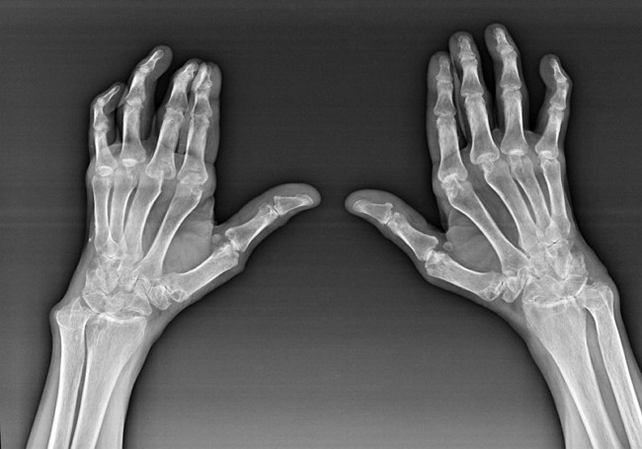

Artritis reumatoide

La artritis reumatoide es una enfermedad en la que el sistema inmune humano daña los tejidos del cuerpo. En otras palabras, la artritis reumatoide es una patología autoinmune. Esta enfermedad también es sistémica, ya que muchos tejidos se ven afectados (músculos, articulaciones, vasos, etc.) y órganos (Corazón, riñones, pulmones, etc.) en el cuerpo.

A pesar del hecho de que la artritis reumatoide es una enfermedad sistémica bajo ella, en mayor medida, las articulaciones sufren, mientras que la lesión de otros tejidos y órganos está en segundo plano. Con esta enfermedad, casi todos los tipos de arbustos pueden verse afectados (Mundos de pulseras, rutas de carpales, metacarpio-falange, juntas interfalánxicas). La lesión suele ser simétrica (aquellos. Las mismas articulaciones se ven afectadas) En ambas manos, acompañado de hinchazón, dolor en las articulaciones dañadas. Por la mañana, durante el levantamiento de la cama, hay cierta rigidez en las articulaciones afectadas, que pueden durar aproximadamente 1 hora y luego desaparecer sin rastro.

Muy a menudo con artritis reumática cerca de las articulaciones afectadas del cepillo (Más a menudo las articulaciones de piano-falange, interfalánxis) Aparecen nódulos reumatoides. Son una formación redondeada ubicada debajo de la piel. En el pincel, estas formaciones surgen con mayor frecuencia en la parte posterior. En la palpación, son densos, inactivos, indoloros. El número de ellos puede variar.